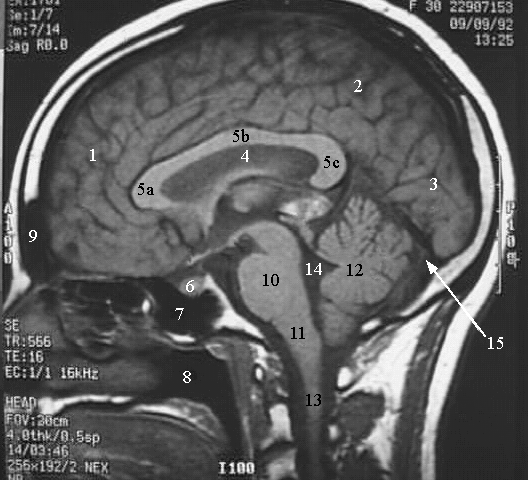

- Frontal Lobe

- Parietal Lobe

- Occipital Lobe

- Septum Pellucidum

- a. Rostrum of Corpus Callosum.

b. Body of Corpus Callosum.

c. Splenium of Corpus Callosum.

- Pituitry

- Sphenoid air sinus

- Nasopharynx

- Frontal Air sinus

- Pons

- Medulla Oblongata

- Cerebellum

- Spinal Cord

- Fourth ventricle

- Sinus Confluence.